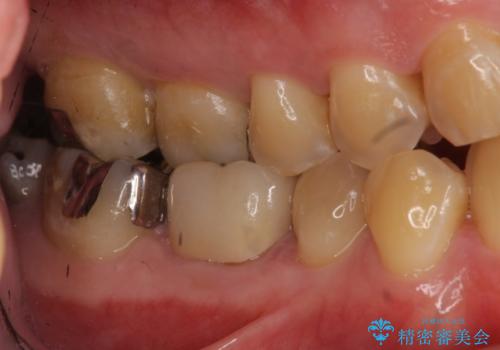

奥歯は神経の治療からやり直し、セラミッククラウンとしました。

手前の歯は1本は虫歯、もう一本もつめものが取れたままでしたので、セラミックインレーとしました。

大臼歯の再根管治療は横浜桜木町歯科院長 大元先生が担当しました。

- 40万円 内訳:右下6(再根管治療13万円、ジルコニアクラウン10万円、ファイバーコア2万円、仮歯1万円)、右下45(セラミックインレー7万円x2本)費用は治療当時の料金となります